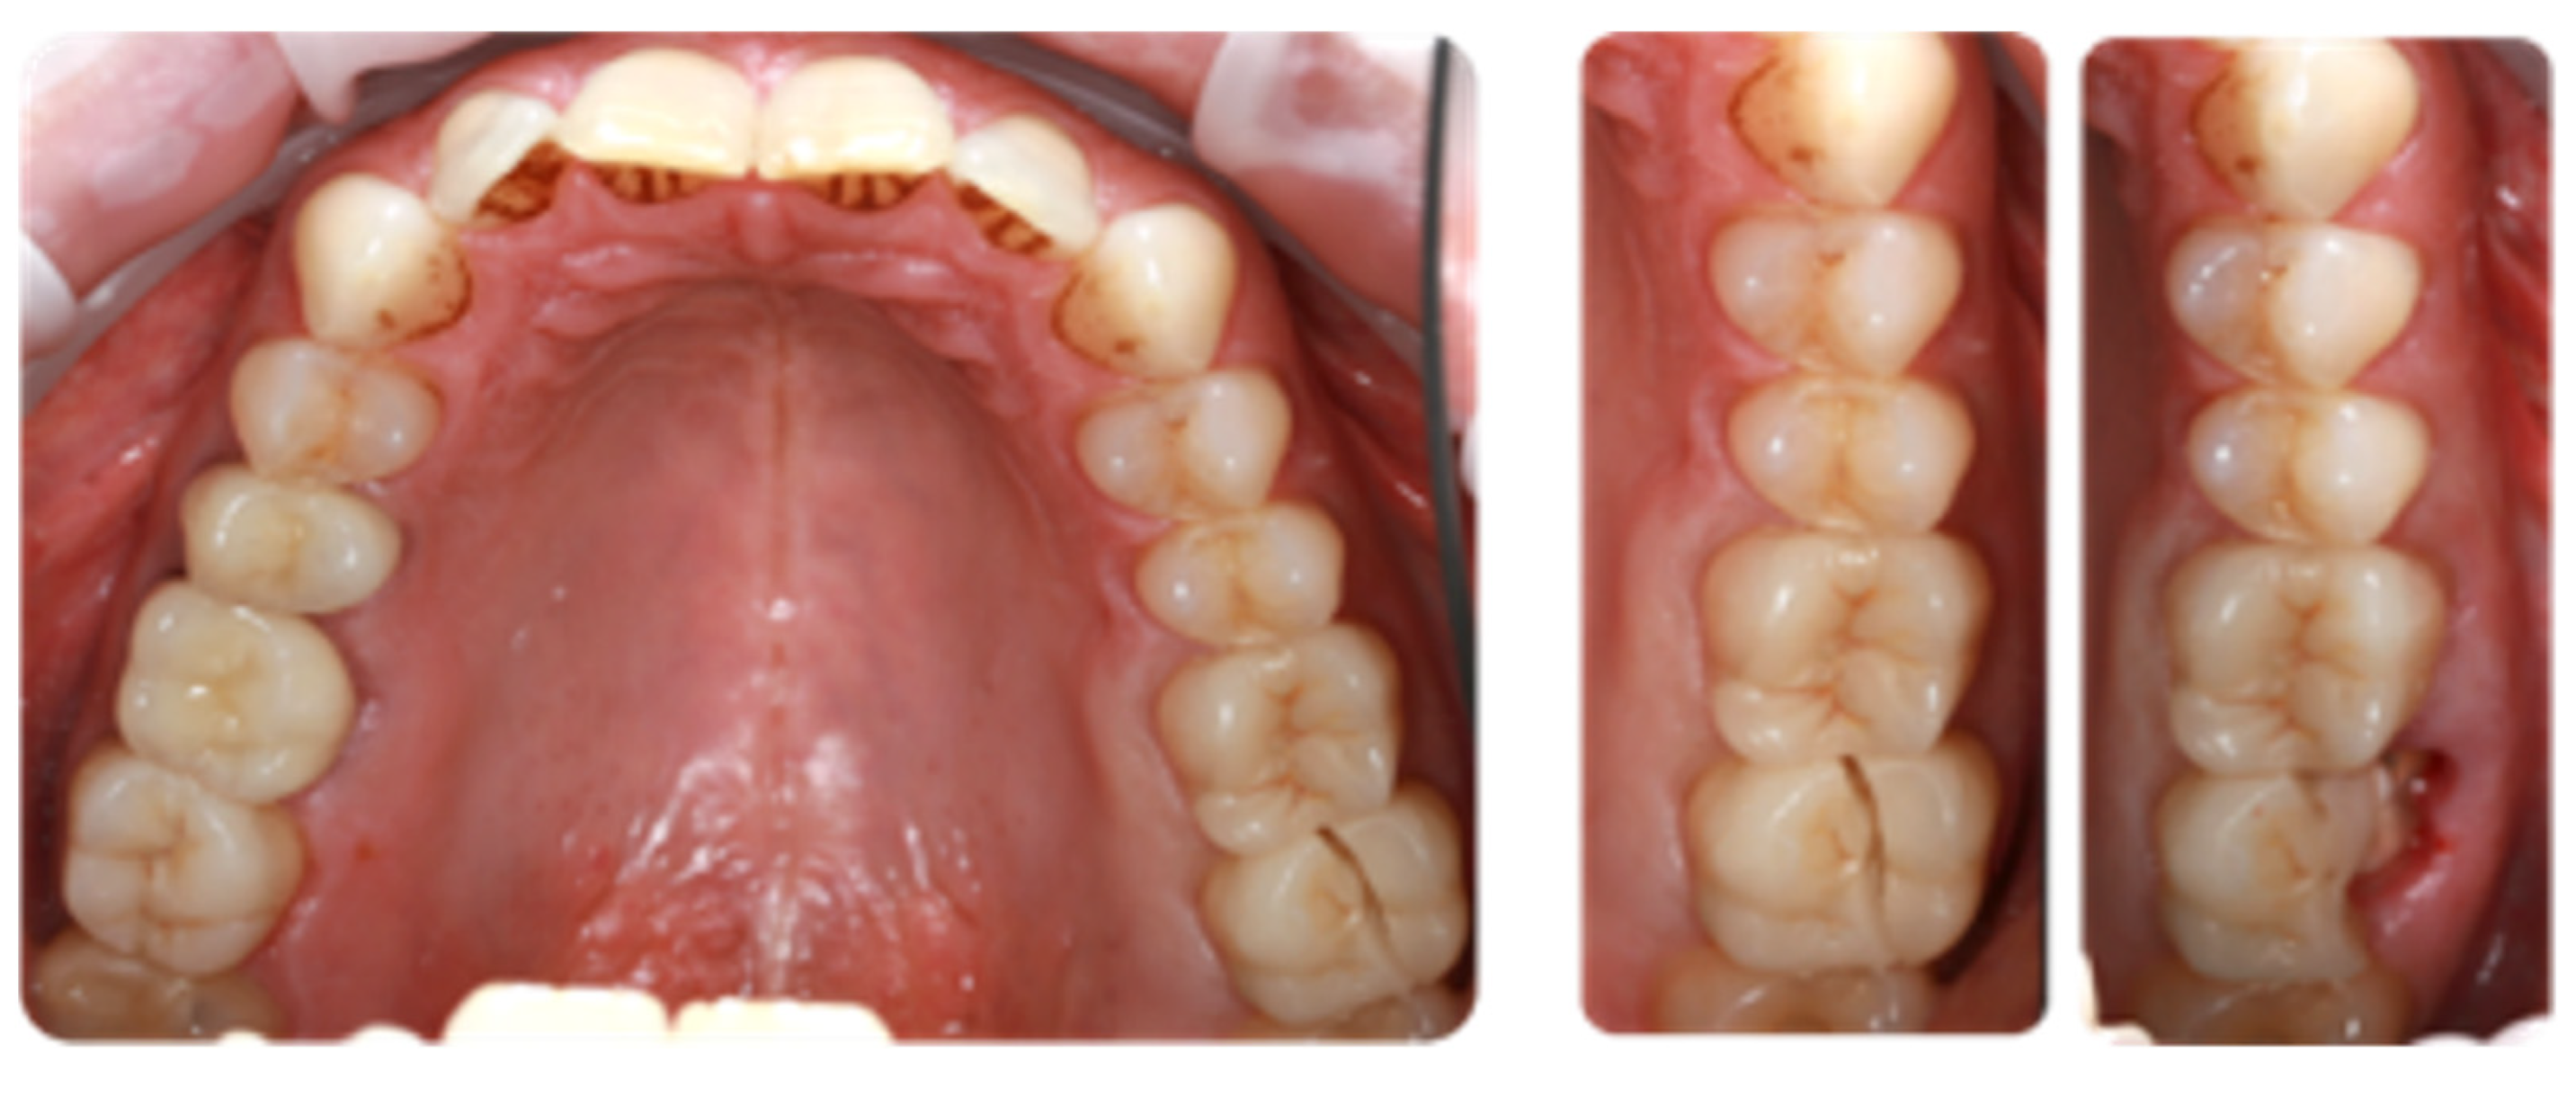

2.1. Cases Selection

2.2. Clinical Preparation Protocol